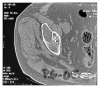

More than twenty years ago, hydroxyapatite (HA), calcium phosphate ceramics, was introduced as a coating for cementless hip prostheses. The choice of this ceramic is due to its composition being similar to organic apatite bone crystals. This ceramic is biocompatible, bioactive, and osteoconductive. These qualities facilitate the primary stability and osseointegration of implants. Our surgical experience includes the implantation of more than 4,000 cementless hydroxyapatite coated hip prostheses since 1990. The models implanted are coated with HA in the acetabulum and in the metaphyseal area of the stem. The results corresponding to survival and stability of implants were very satisfactory in the long-term. From our experience, HA-coated hip implants are a reliable alternative which can achieve long term survival, provided that certain requirements are met: good design selection, sound choice of bearing surfaces based on patient life expectancy, meticulous surgical technique, and indications based on adequate bone quality.